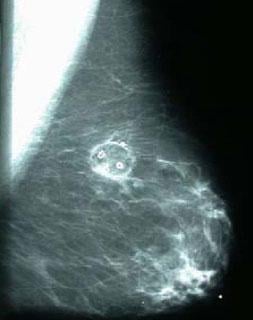

Novilase Breast Therapy uses direct laser therapy to treat fibroadenomas. The system aims to treat these noncancerous tumors while minimizing risks and maintaining the breast’s natural shape and feel.

“With the X-ray guided laser technology we have today, lumpectomy is overkill,” said Dr. Dowlat. “Lumpectomy creates a significant scar and can deform the breast when you take the tumor out. Fibroadenomas can be precisely ablated with a laser, giving a superior result and less medical risk than lumpectomy. This is a great boon for patients because they can have their benign tumors treated without significant consequences for their health or appearance.”

• Less infection risk. The procedure involves the insertion of a laser probe and a thermal probe through two 1/8- inch skin nicks. The small size of the nicks keeps the infection risk extremely low. In contrast, a lumpectomy uses a 2 inch-to-3 inch incision, which creates a greater risk of infection.

While Novilase uses direct laser therapy to treat fibroadenomas, laser ablation has been successfully used to treat benign prostate tumors. Novilase also uses the same image guidance for breast biopsy.